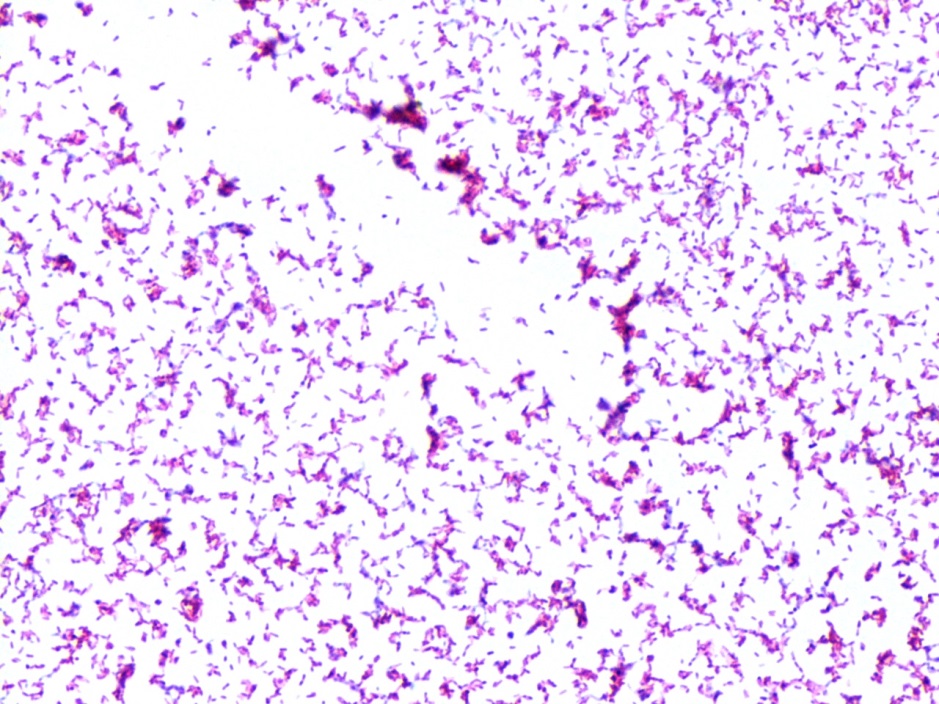

“Cording” is term used to describe twisting, serpentine appearance of Mycobacterium in liquid broth culture. And, at least in many places, it is taught to budding microbiologists and infectious disease clinicians as a hallmark characteristic of Mycobacterium tuberculosis (Mtb).

Cording phenotype is distinct from “clumping.” With cording, bacilli lay in tightly packed parallel strands, and not clumped together showing random bacilli orientation.

Importantly, cording in non-tuberculosis Mycobacterium species is 1) actual cording and 2) visually indistinguishable from cording seen in Mtb.

In my laboratory, (Spokane, Washington, USA) we regularly see isolates of Mycobacterium abscessus, a rapid growing mycobacterium species, with clear cording morphology. These twisting structure are clearly cords, not just clumps.